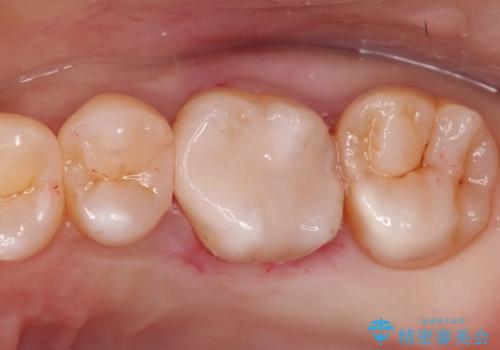

金属の詰め物を外してセラミックインレーに

- 矯正終了後に見た目をきれいにしたい希望があり、金属の詰め物を外してセラミックにて修復処置をしました。

セラミックインレーは天然の歯に近い透明感や色調を再現することが可能です。治療では自然な見た目になるまで追及しますので患者さんには非常に満足していただけました。